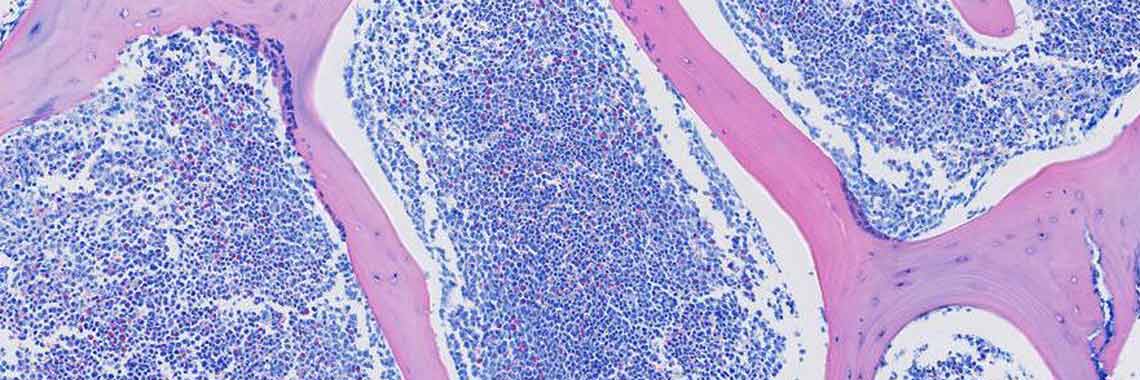

Praxisnahe Fortbildungen in der mikroskopischen Diagnostik hämatologischer Erkrankungen

In den Kursen wird die mikroskopische Diagnostik hämatologischer Erkrankungen praxisnah, vergleichbar der Arbeit im eigenen Labor, praktiziert.